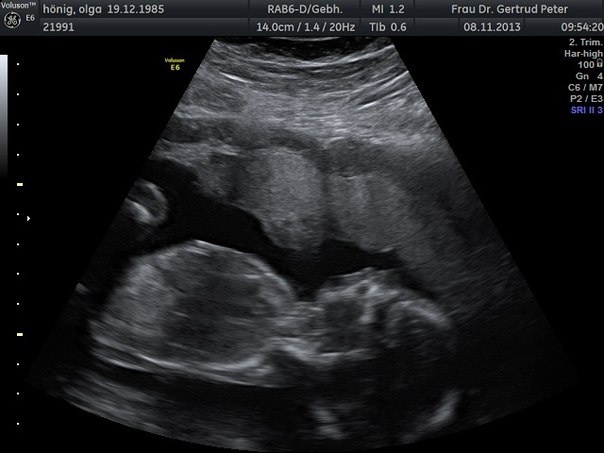

Анализы, скринингиВот и прошел наш второй скриннинг, сегодня виделись с мужем с нашим Мишуткой. Так как шевелений я не чувствую, я очень переживала, как там наше сокровище. Как только сегодня увидела, чтосердечко бьется и он дрыгает ручками и ножками, у меня из глаз покатились слезы... я ничего с собой не могла поделать, муж как мальчишка все разглядывал, умилялся, а я как дура лежала со слезами на глазах. Но минут через 5 все прошло и я просто стала наслаждаться своим сыночком. Он тер глазки ручкой, высовывал язычок и сладко-сладко зевал. Болтал ножками и плавал как рыбка. Какой же он сладкий, я прямо, девочки, счастлива, что испытываю такие неописуемые чувства. Мы с мужем только о нем и говорим, каким он будет и как нам будет хорошо и тепло втроем.

Результаты скрининга меня порадовали, даже очень, все вроде у нас хорошо, весит наше золотце уже 253 гр( завтра 19 недель) , сердцебиение 148 уд в минуту., обхват головки в норме, с сердечком все в порядке,желудок посмотрели, как почки работают, позвоночник, животик, мозг.